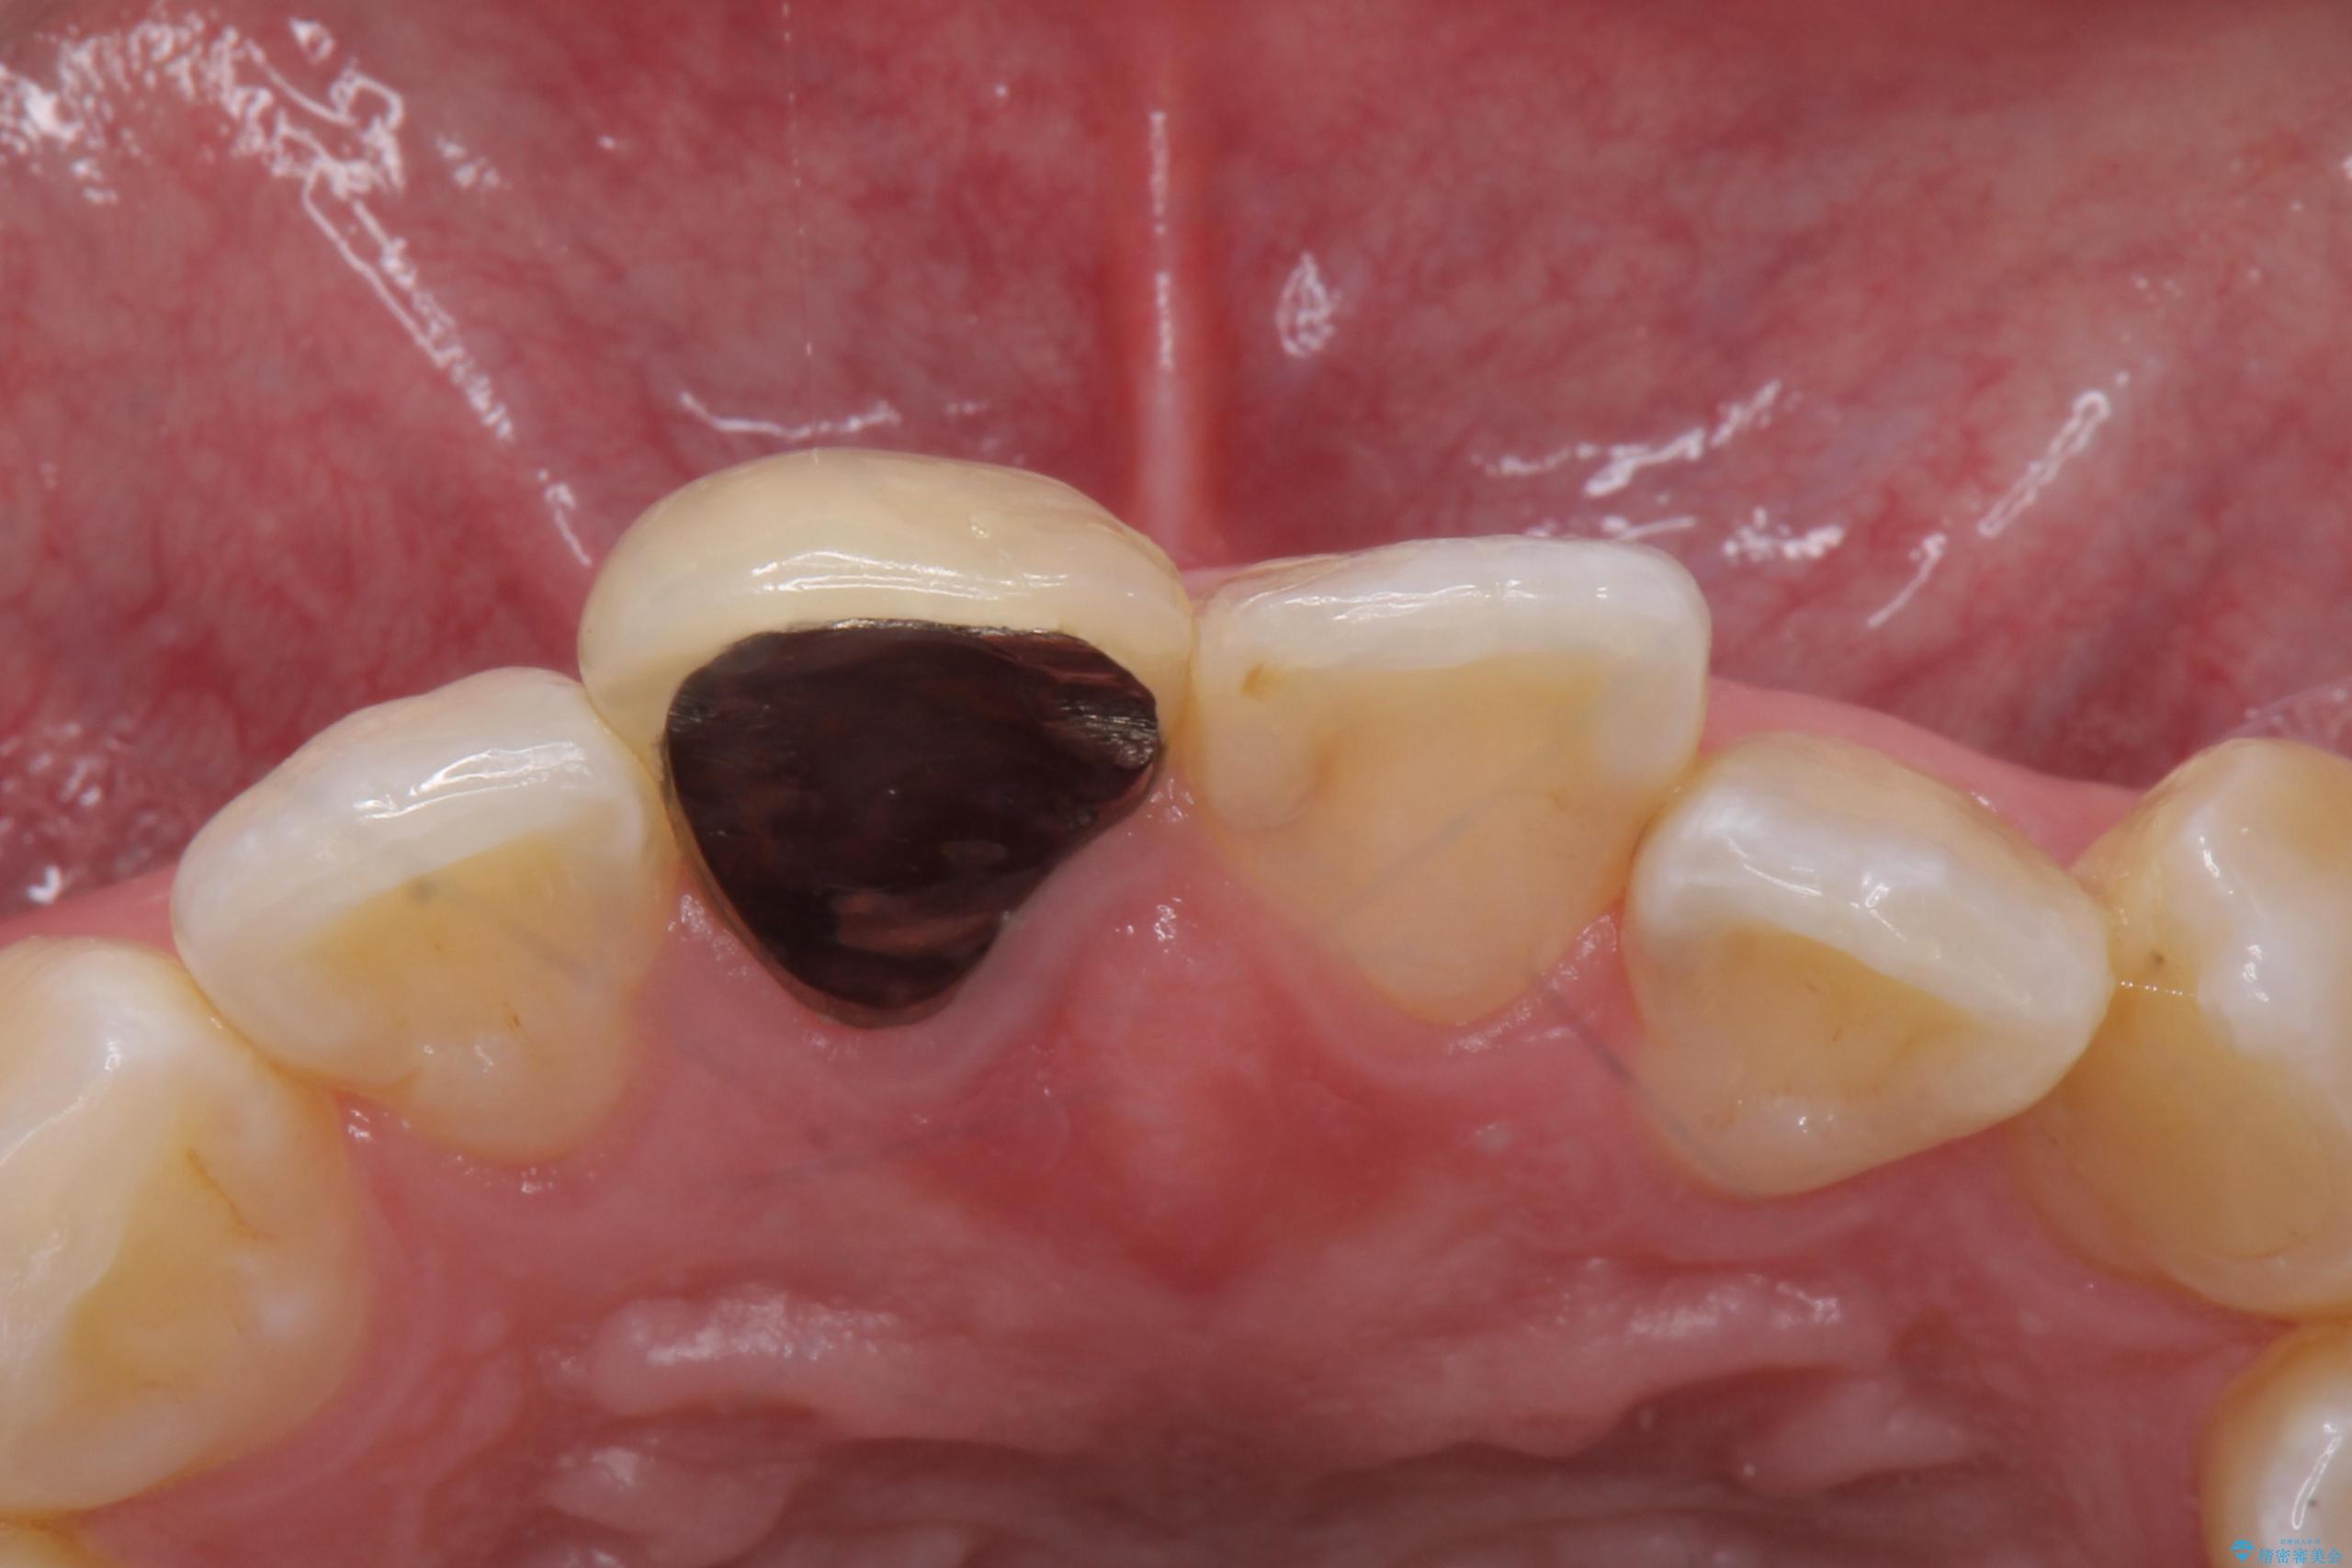

- 前歯のかぶせ物の色が気になるとのことで来院された患者様です。

セラミッククラウンで作り変えていきます。